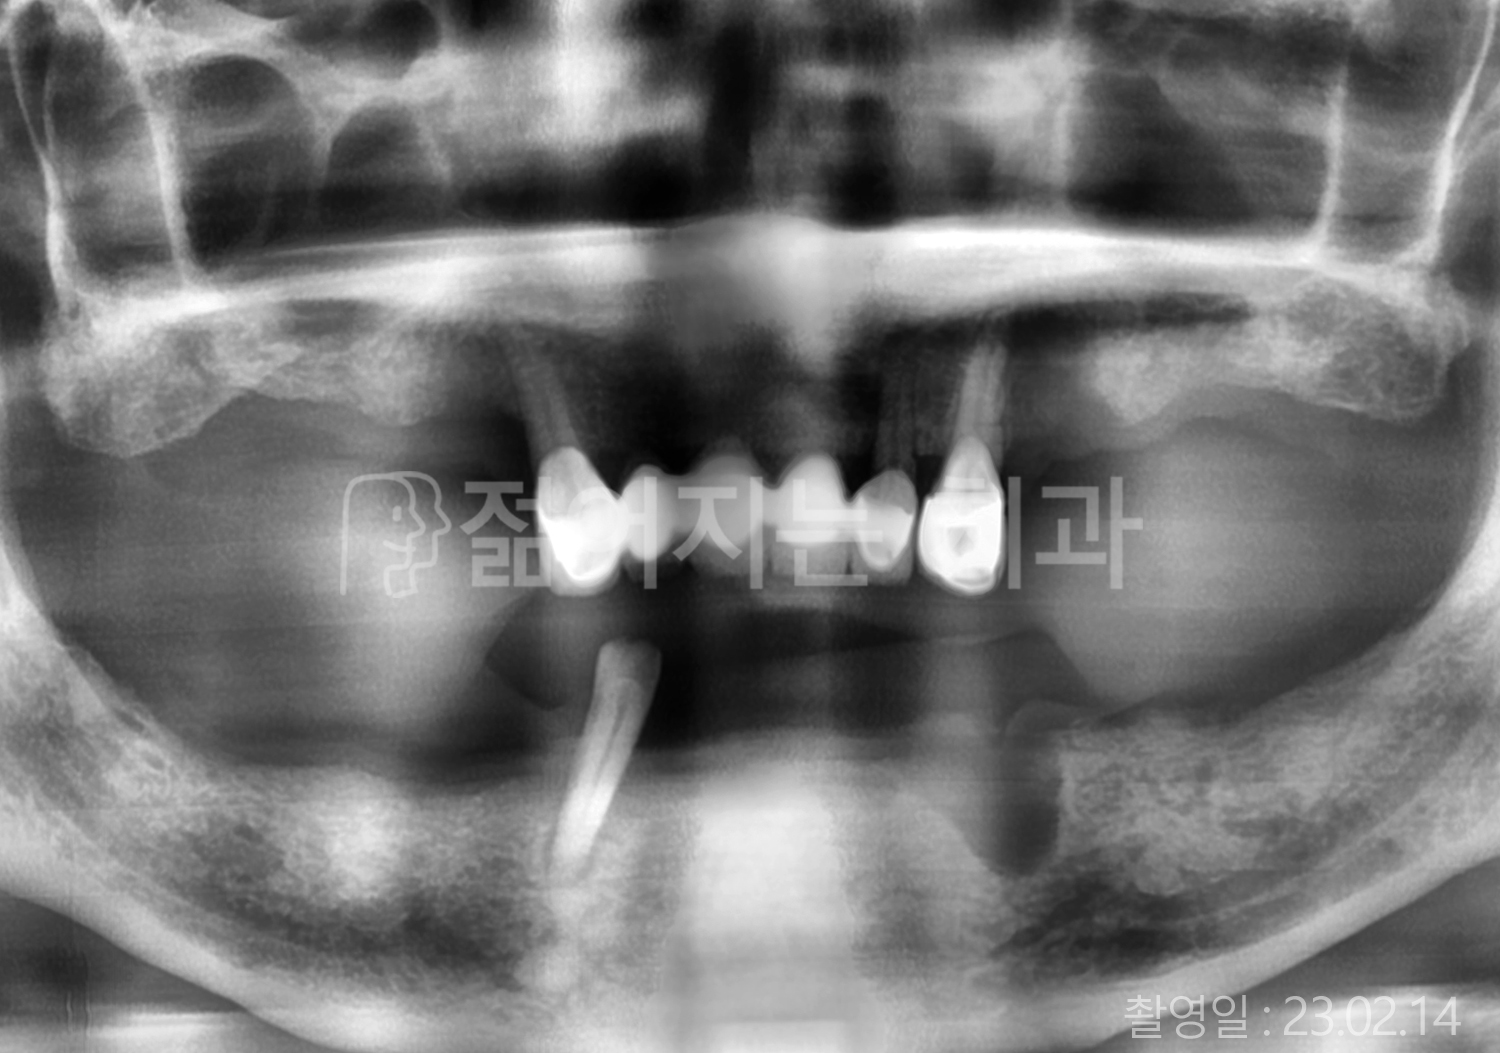

60대 고혈압, 고지혈증

전체치아 10개 이상 임플란트

60대 고혈압

70대 고혈압